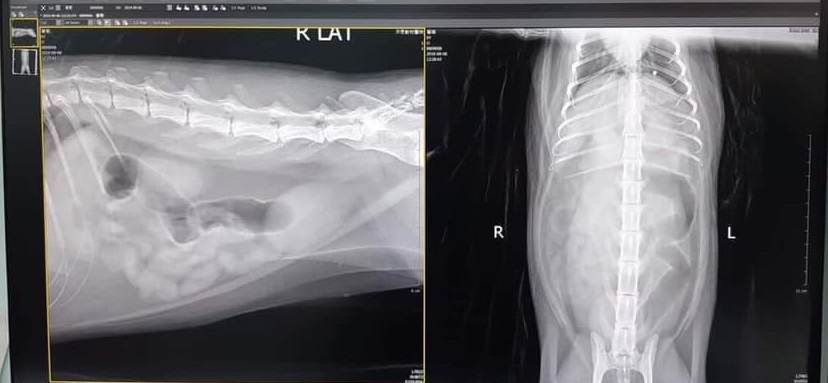

2019年的9月初葡萄因突然嘔吐數次,於是於9月6日約診沐恩醫院檢查,葡萄看診很緊張,只好全程用大毛巾蓋住頭臉,醫師進行了胰臟炎快篩、血檢、超音波、X光檢查,除了白血球及血糖偏高、輕微脫水,並無發現其他異常,醫師給葡萄開了制酸劑及打皮下補充水份,並囑咐調整飲食多加觀察。

葡萄因多次嘔吐所以約診就醫,進行胰臟炎快篩,數據顯示並無發炎;血檢結果,唯白血球偏高且有些微脫水導致血糖偏高,其餘數值皆在正常範圍內。進行超音波檢查,腸胃也無異常,且胃部是整個空空的。